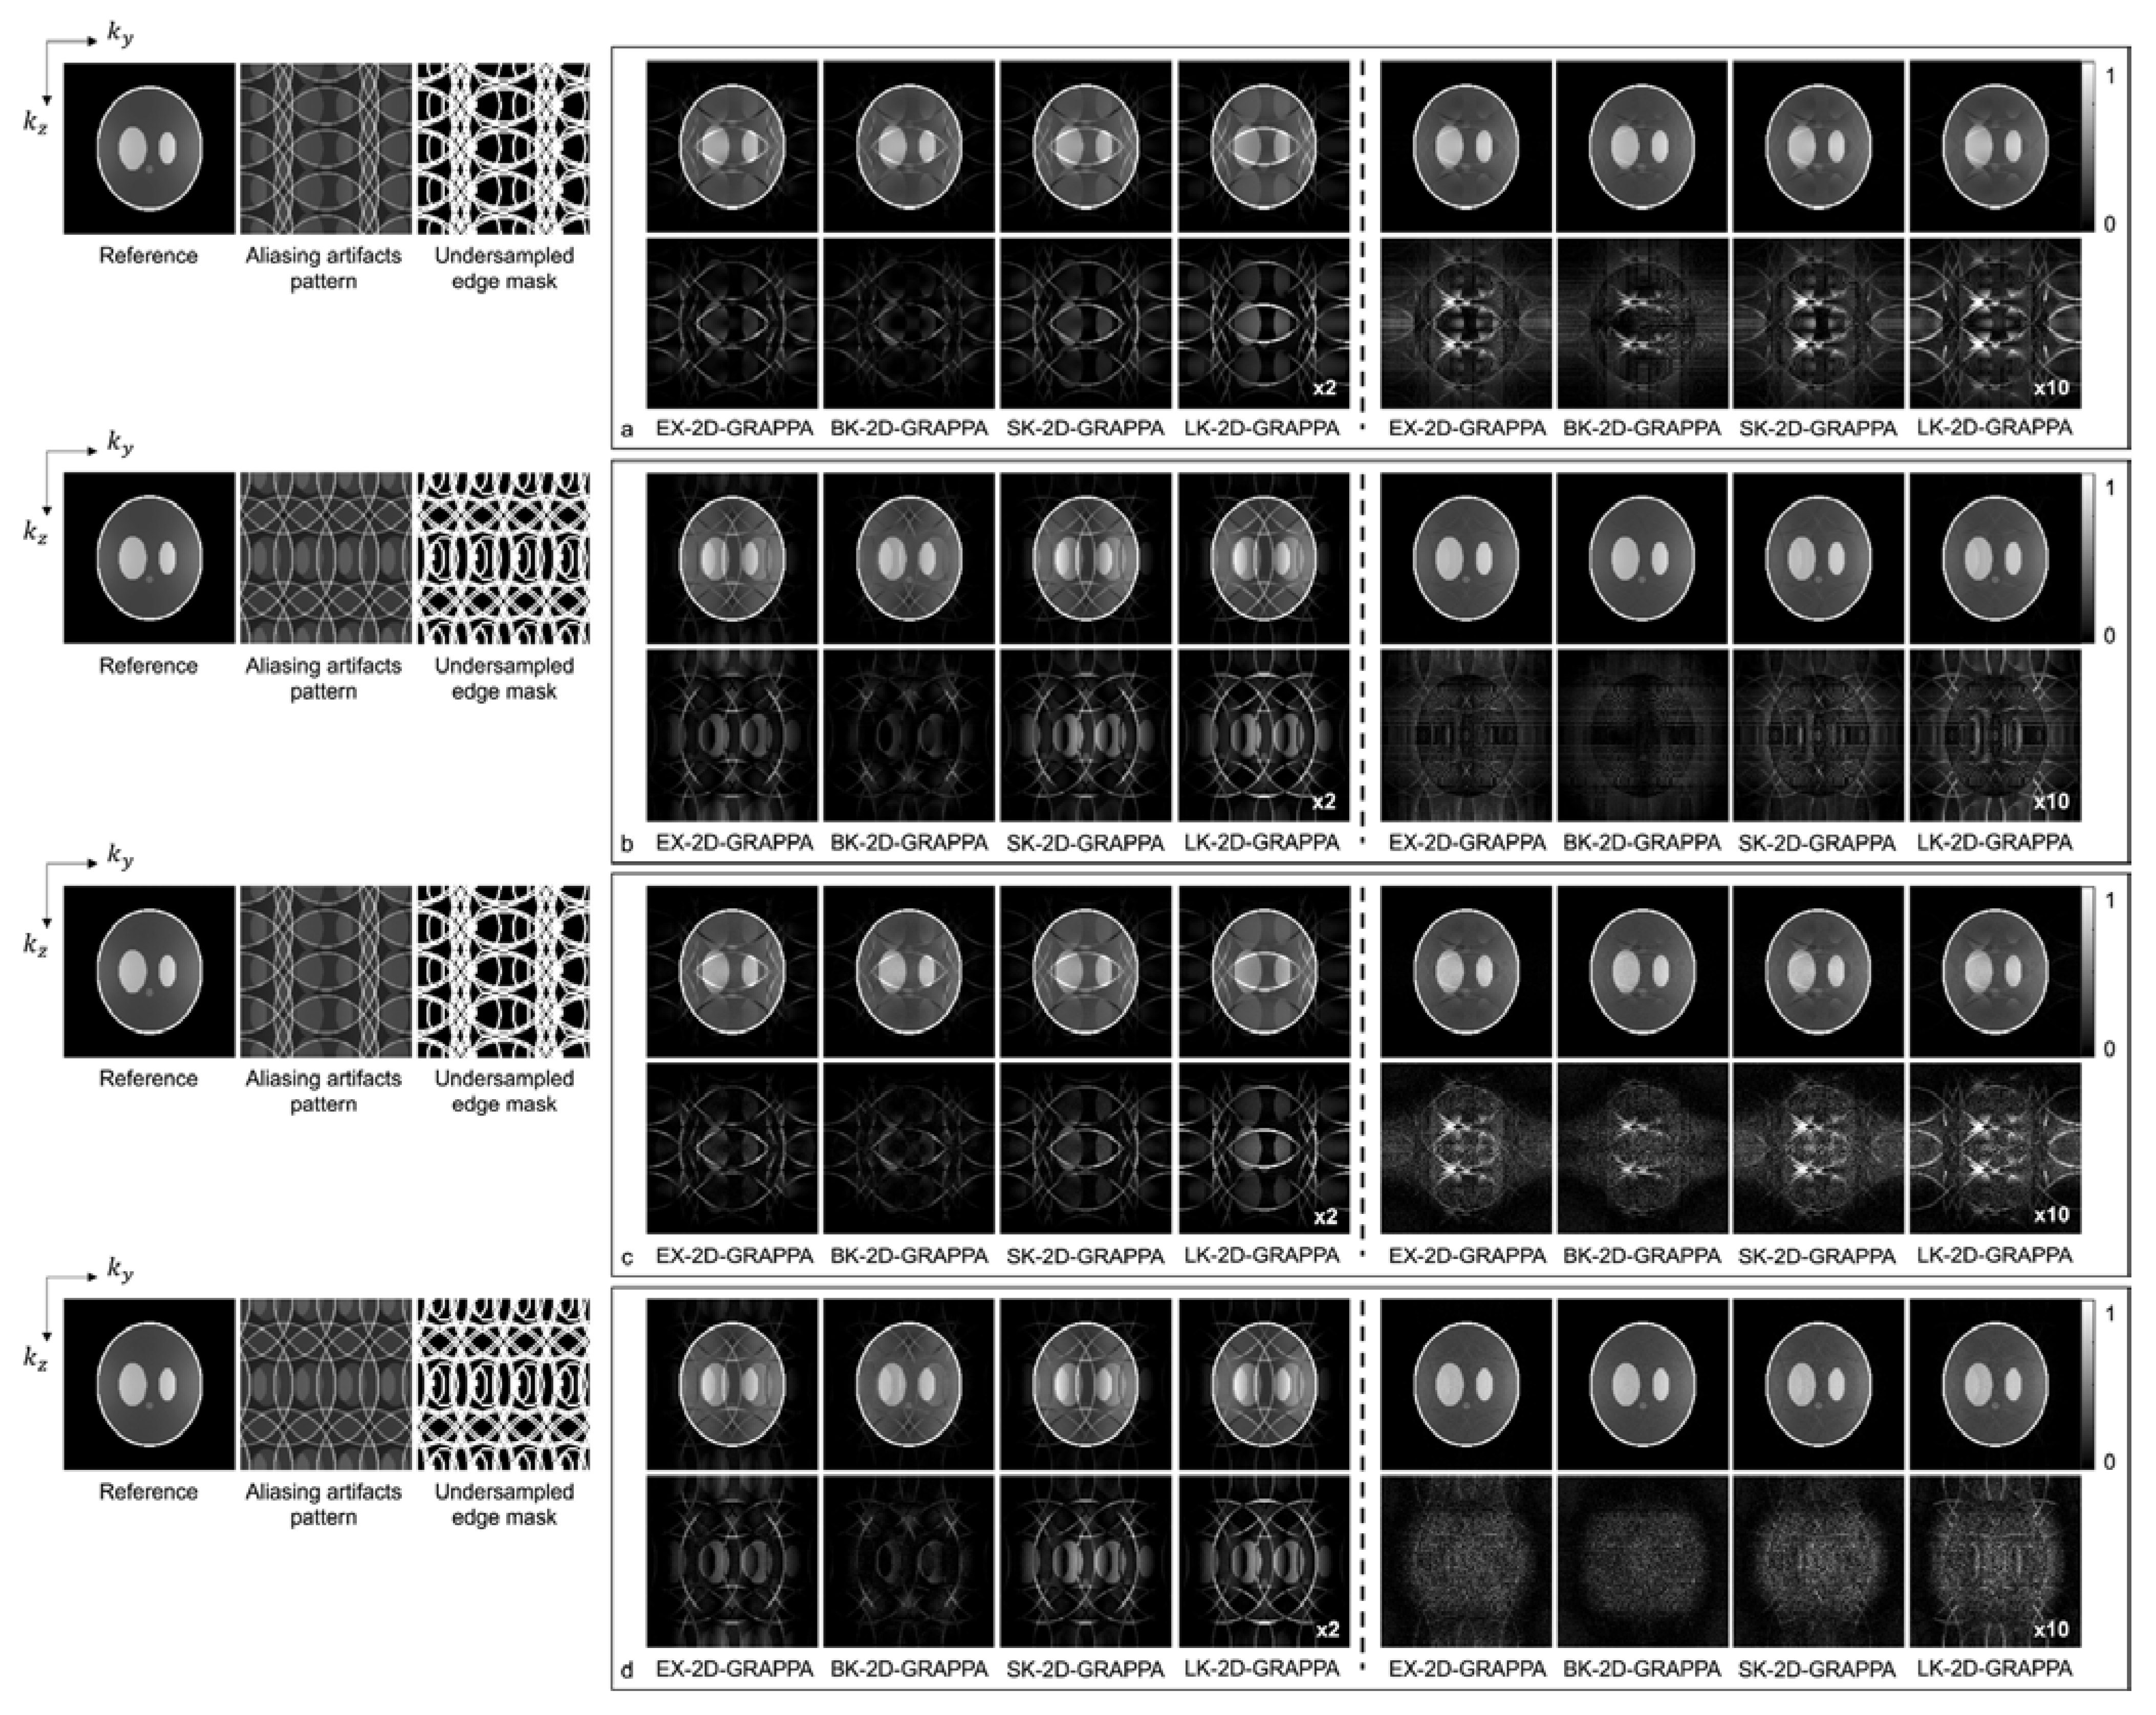

4. Results